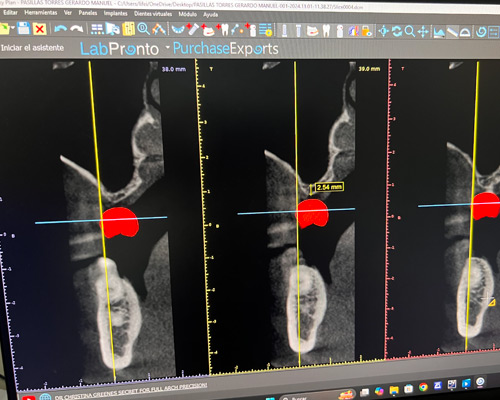

• Surgical and prosthetic training on Shining 3D Facial scanner protocols.

• Surgical and prosthetic training on magnetic full arch digital workflow.

* Dr. Mongalo will review all Ct-scans and 3D images of surgical patients operated on daily.